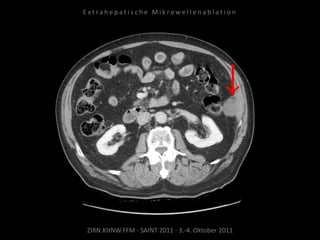

Bildgebung vor MWA:

CT vom 14.07.2010

Metastase lateral der linken Niere

nahe Colon descendens progredient.

Situation:

Metastasierung über längeren Zeitraum

lokal begrenzt,

1 Metastase progredient.

Organnahe Lage in unmittelbarer

Nachbarschaft zur linken Niere bzw. zum

Colon descendens.